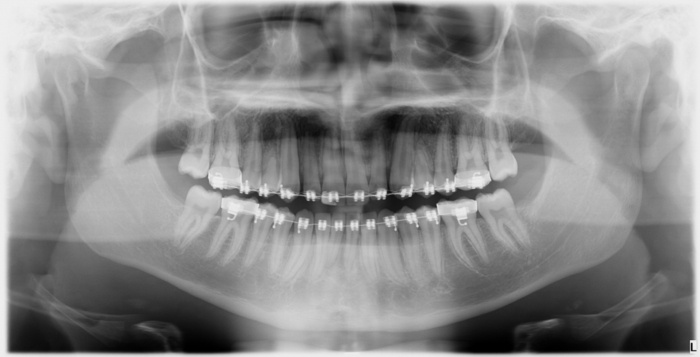

Rx Panorâmico - Caninos inclusos e intra-ósseos - Clínica Cliniface

Rx Panorâmico - Caninos inclusos e intra-ósseos